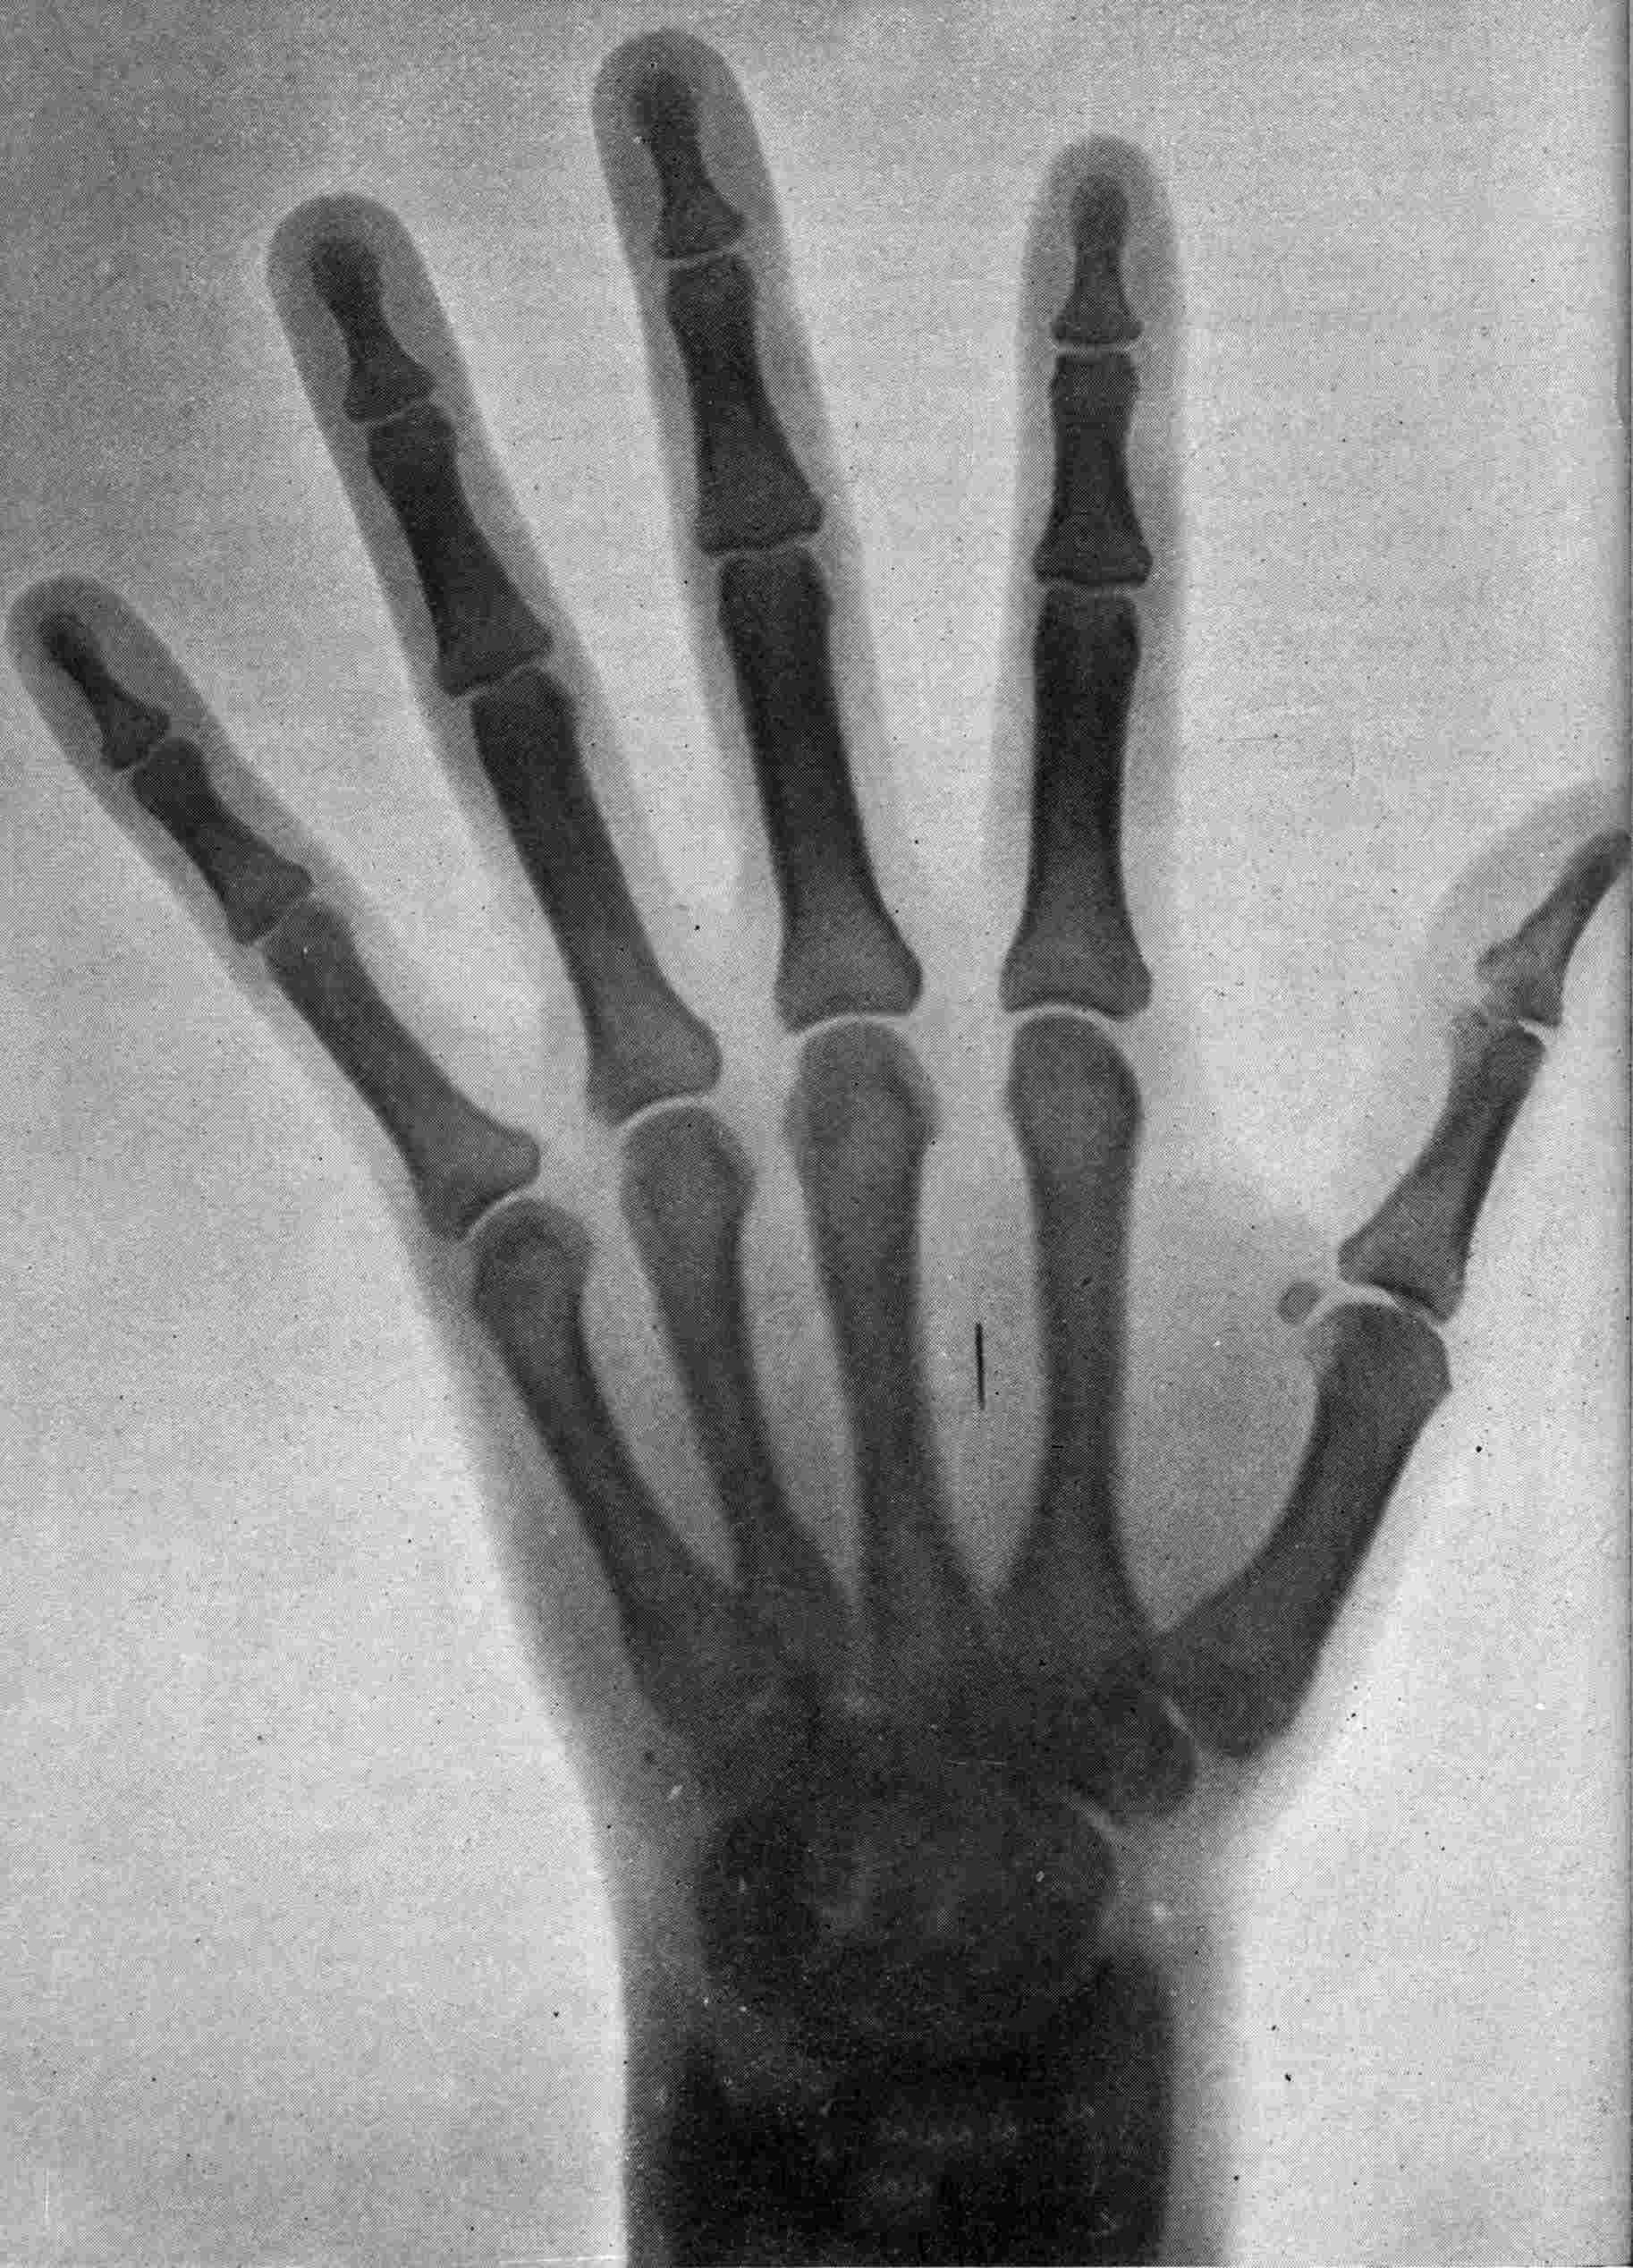

Fig. 1.—Head.

FROM SCIAGRAPHS BY PROF. DAYTON C. MILLER. § 204.